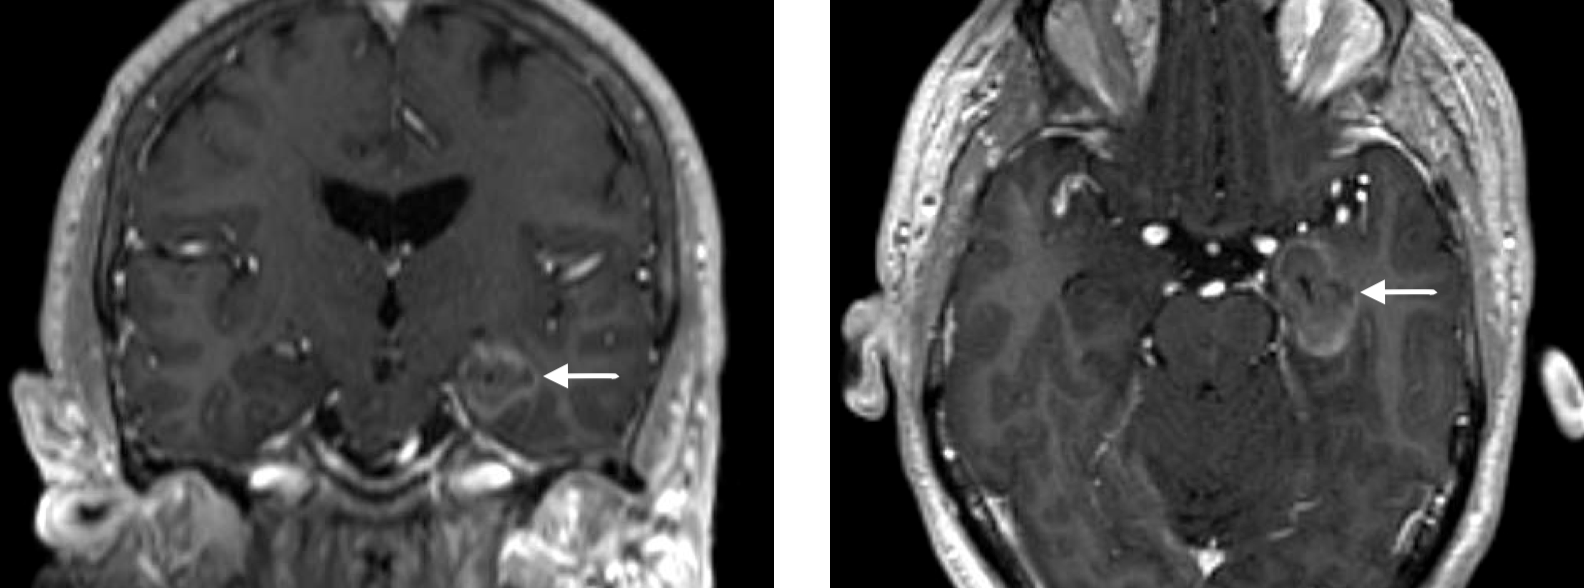

Temperature changes in the hippocampus and amygdala viewed on an MRI scan during a laser interstitial thermal therapy procedure (LITT or laser ablation) for medial temporal lobe epilepsy

Example of how the MRI is used to monitor temperature change in the brain tissue that we are targeting in a laser ablation procedure. Images courtesy of Medtronic.

Damage estimate in the hippocampus and amygdala viewed on an MRI scan during a laser interstitial thermal therapy procedure (LITT or laser ablation) for medial temporal lobe epilepsy